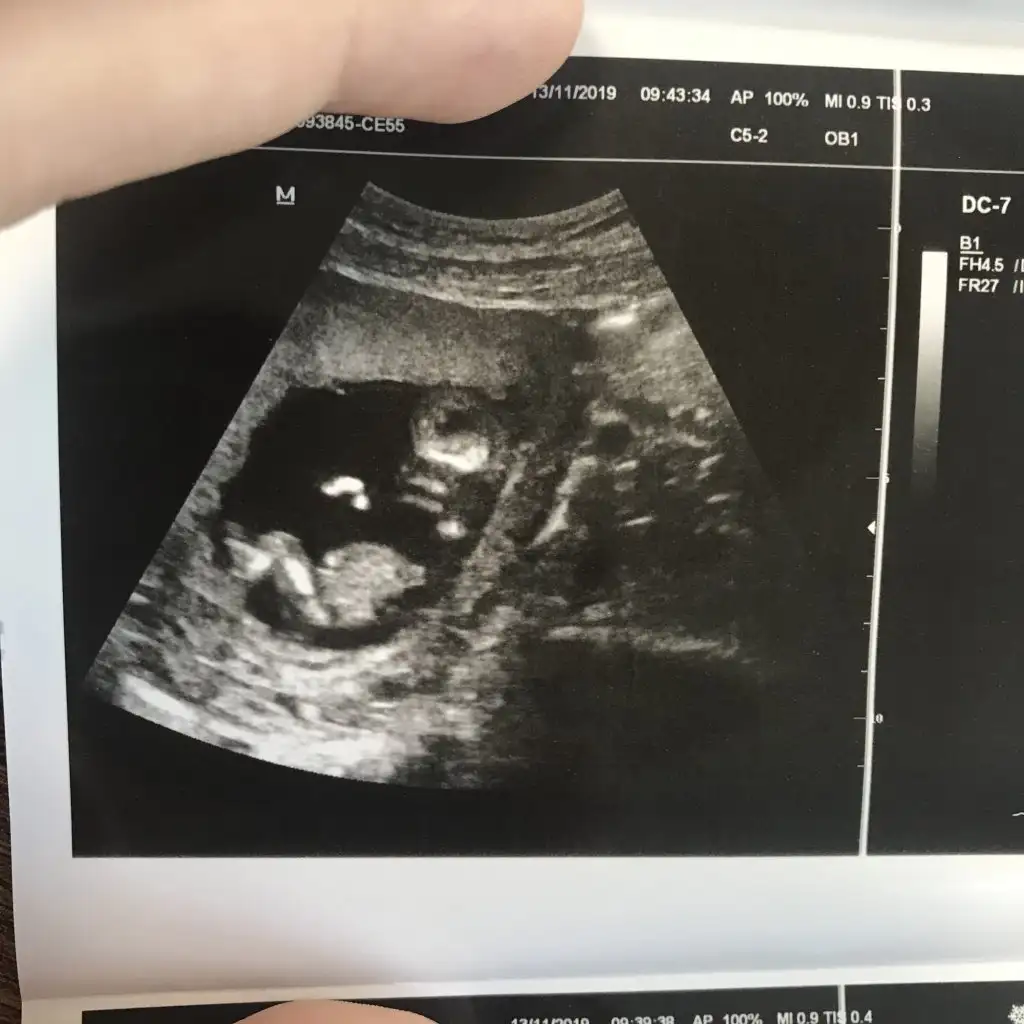

dr soylemeden siz gorun genital nub teorisi ( bebegin cinsiyeti)

Nub bilen var mi kizlar

Arkadasimin bebisi cok merak ediyor

Merhaba, 12 haftalık net çıkmamış ama tek görüntü

bi tahmininiz var mı ?